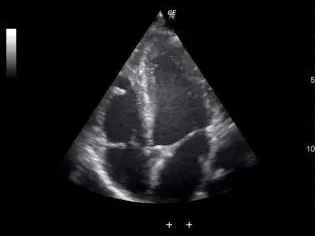

小孩出生的時候就有做全部自費的超音波檢查,

而帶小孩去做心臟超音波時,

醫生表示小孩心臟有破洞0.5公分,